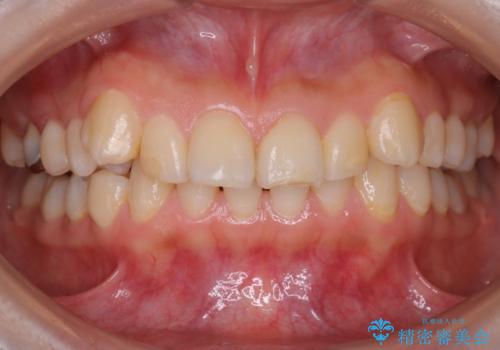

【ワイヤー矯正】前歯が出てるのをなおしたい。

- 前歯の凸凹を主訴に来院されました。